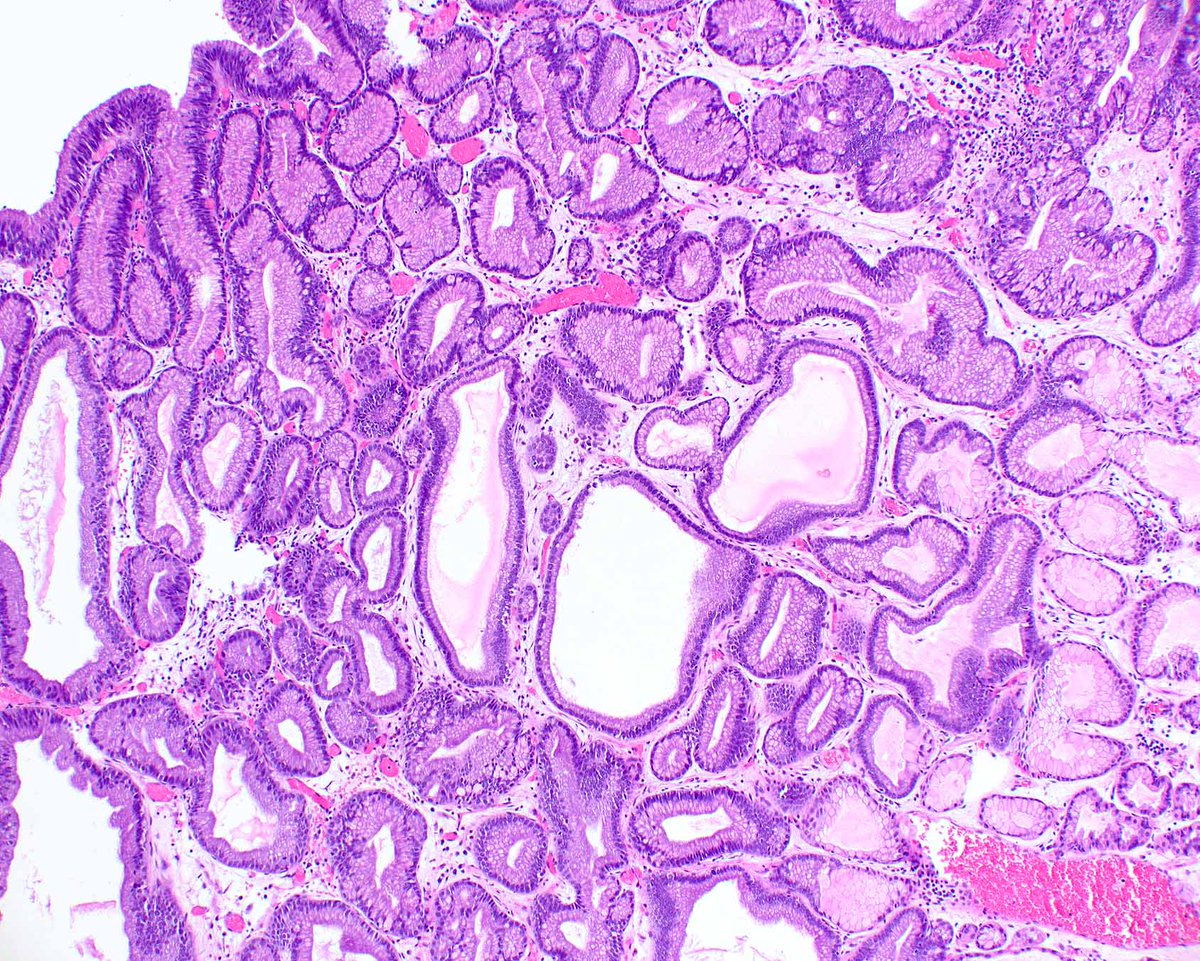

A never-ending obsession with pyloric gland adenomas is a benign problem.  This one arose in otherwise normal gastric oxyntic mucosa and coats the surface!  They are also associated with autoimmune gastritis and probably arise from pseudo-pyloric metaplasia in that setting.